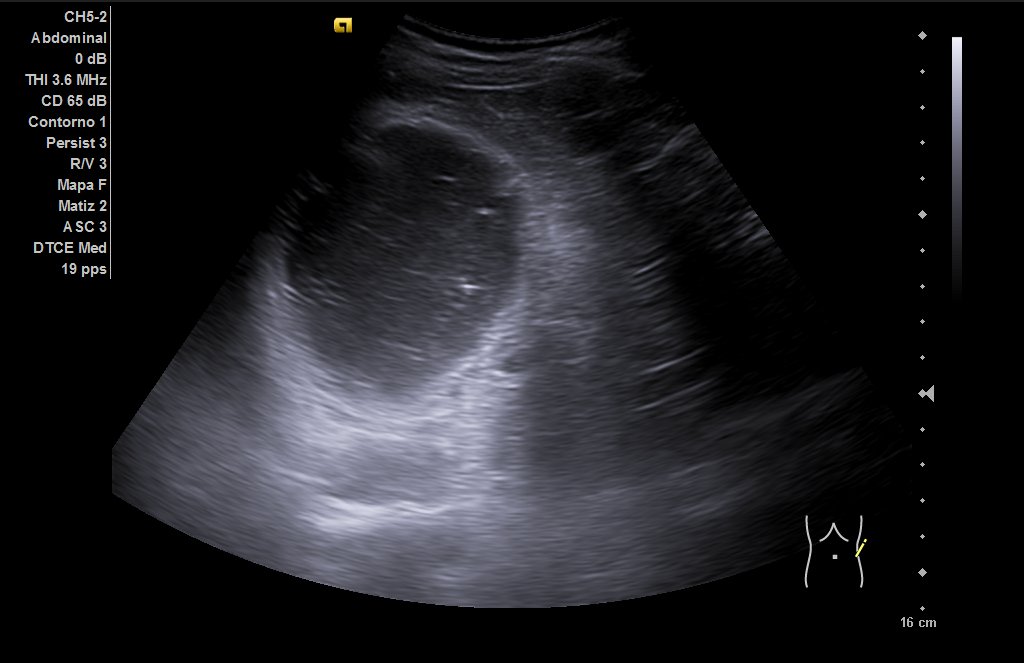

Riñones de tamaño y ecoestructura normales, con buena diferenciación parénquima-seno en polo inferior de riñón derecho, quiste simple de aproximadamente 6 centímetros de eje mayor (ya conocido) y en riñón izquierdo, quiste cortico-sinusal de menos de 2 cm (también conocido). Próstata de 44 gramos. En hipocondrio izquierdo observamos imagen redondeada con contenido ecogénico, con tractos hiperecogénicos en su interior que podría corresponderse a dilatación ángulo esplénico de colon.